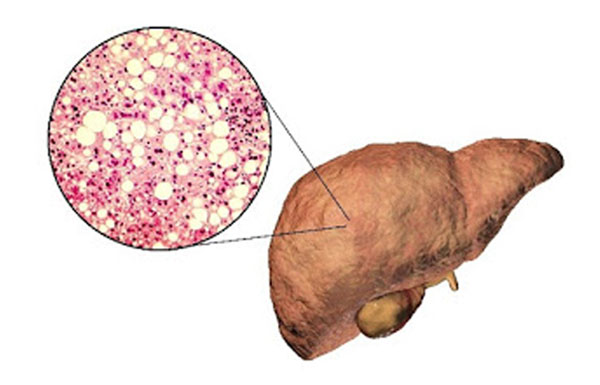

Non-Alcoholic Fatty Liver Disease is increasingly common worldwide and linked to obesity, diabetes, and metabolic syndrome. Recent research underscores that MASLD treatment centers on lifestyle modification and drug therapies targeted at metabolic risk factors.